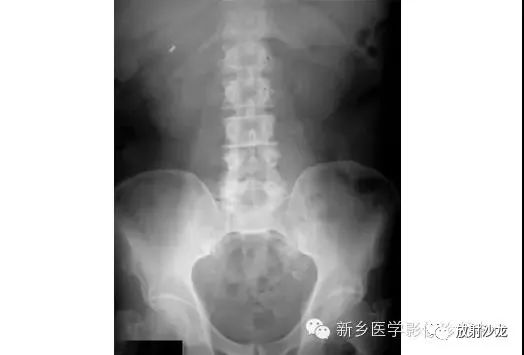

病例七:

上图为9岁,腹痛、呕吐患儿所做的腹部平片。该患儿有阑尾炎合并腹膜炎病史。影像学异常是什么,最有可能的病因是什么?腹部X线片显示小肠襻的明显扩张、环状襞的消失,这与小肠梗阻的诊断相一致。该患儿既往有腹膜炎病史,梗阻是由腹腔粘连造成的。这个孩子最终经保守治疗康复。